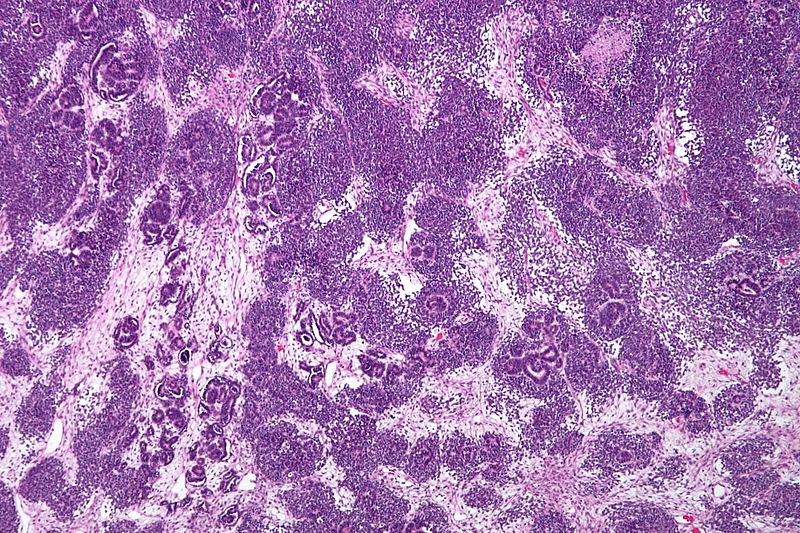

Wilms Tumor

Wilms tumor is a malignant kidney tumor composed of primitive glomeruli, tubules, and stromal cells blastema which is an immature kidney mesenchyme.

Wilms tumor is associated with WT1 mutation, especially in syndromic cases.